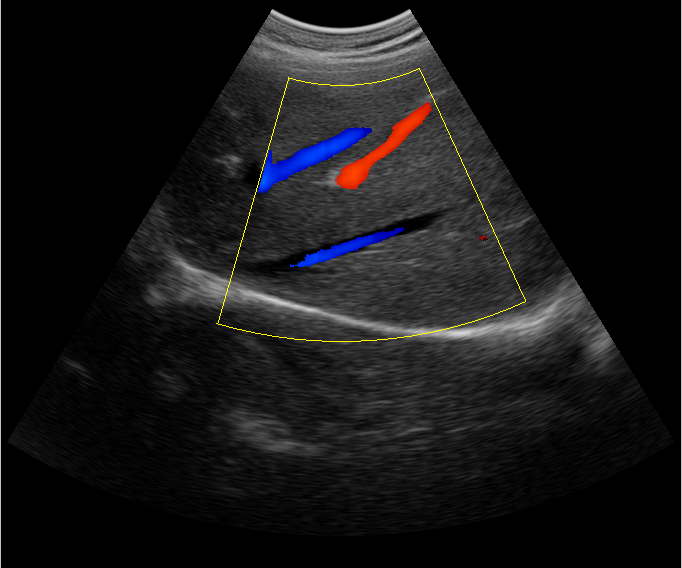

B超檢查主要是檢測(cè)肝臟的外形、大小、膽囊、門靜脈、回聲粗線等問(wèn)題。由于乙肝病毒造成肝細(xì)胞破損嚴(yán)重,肝細(xì)胞出現(xiàn)問(wèn)題,發(fā)生異常外形就會(huì)改變,通過(guò)B超檢查就能很清楚的檢查出肝臟受損的程度,以及肝臟的大小是否改變,肝臟是否發(fā)展為肝纖維化、肝硬化等。還可以檢查門靜脈主干內(nèi)徑是否增寬等情況。

肝臟B超還可以通過(guò)肝臟的門靜脈、回聲粗線、膽囊等指標(biāo)來(lái)診斷病情。由于肝炎病毒長(zhǎng)期侵害會(huì)造成肝細(xì)胞破損嚴(yán)重,肝細(xì)胞出現(xiàn)異常,肝臟發(fā)生異常時(shí)外形就會(huì)改變。通過(guò)肝臟B超檢查就能很清楚地看出肝臟的受損程度,以及肝臟的大小、形態(tài)、回聲等是否正常。有利于肝臟的疾病的正確診斷。